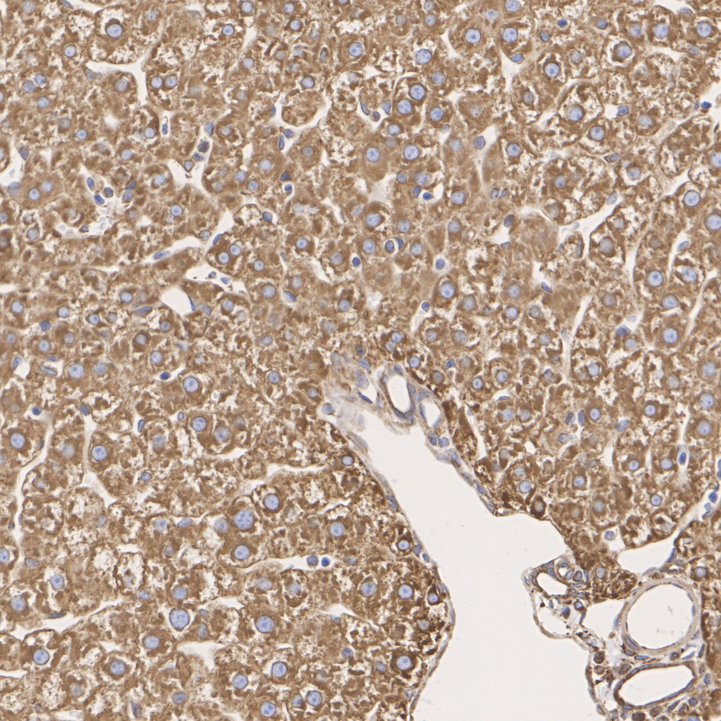

Catalog# M1506-2

GRP78 / BIP Mouse Monoclonal Antibody [C9-9]

IHC-P